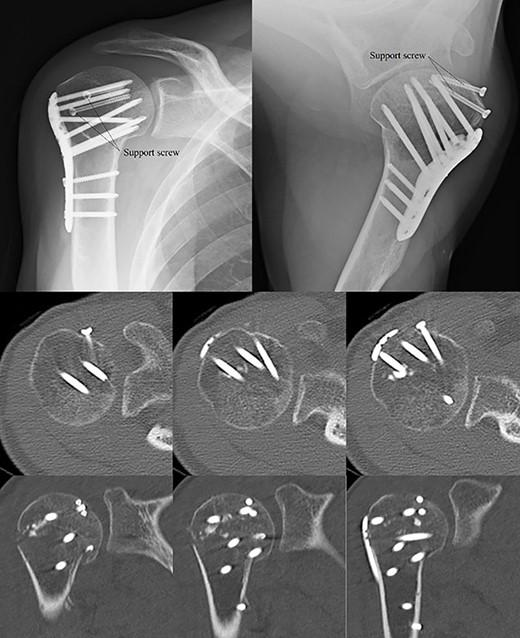

Postoperative radiographic and CT evaluations showed reduced fractures on the humeral head and surgical neck (Fig. 7). At 24 months of postoperative follow-up, radiographic and CT evaluations showed no signs of osteoarthritis or reimpression (Fig. 8). Two years after the primary surgery, we performed implant removal at the patient’s request (Fig. 9). When performing implant removal, we additionally performed a second-look evaluation with arthroscopy to assess the degree of healing in the joint. We noted no impression or exposure of cartilage callus on either side of the humeral head or glenoid (Fig. 10).

Postoperative X-ray and CT scan showing sustained anatomical reconstruction of articular surfaces and no signs of osteoarthritis.

Two years later, pre-implant removal CT showed that the reduction in the depressed surface had been maintained with no obvious arthritic changes.

Post-implant removal X-ray showing that the alignment had been maintained.